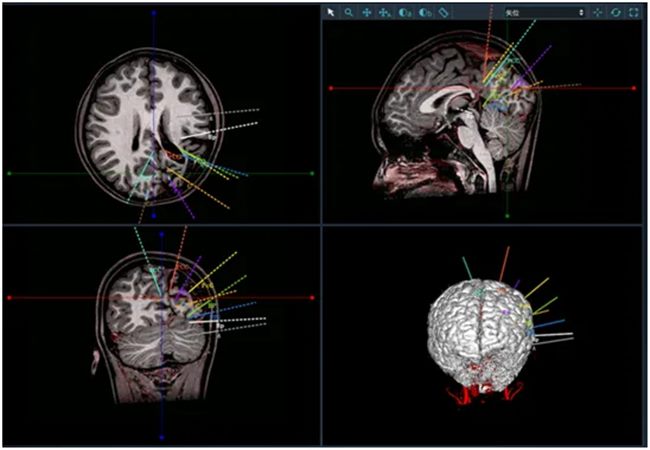

确定患儿左侧半球功能后,由于左侧还有部分功能,为了尽可能减少对功能区的损伤,李培栋主任医师决定为患者进行立体定向脑电图(SEEG)电极植入。根据患者长程脑电记录、影像脑网络分析和临床表现,共计选择10根电极置入,精准记录致痫灶,在SEEG精准定位下,最终切除病灶。